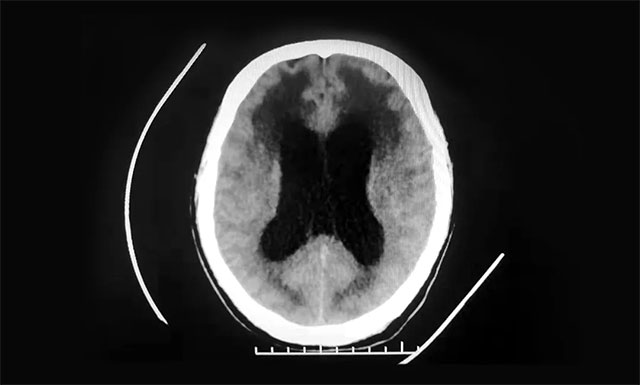

▲ 患者腦室明顯擴(kuò)張,腦脊液已滲入腦組織

醫(yī)院神經(jīng)外科6A病區(qū)侯增欣主任團(tuán)隊(duì)結(jié)合患者既往病史,有針對性地對患者開展了系統(tǒng)的檢查,余先生的定向力、計(jì)算力和記憶力均有所下降,精神狀態(tài)差,意識(shí)障礙較為明顯。行CT檢查可見,患者腦干體積縮小,腦室系統(tǒng)中度擴(kuò)張,充盈的腦脊液已部分滲入了腦組織,形成間質(zhì)性腦水腫,情況比較嚴(yán)重。